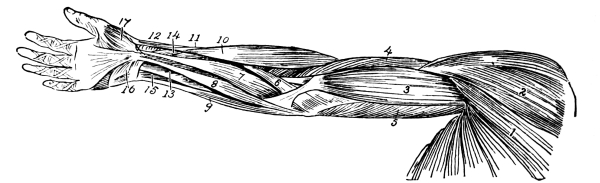

| The Upper Extremities | 171 |

The Shoulder Girdle, 171—The Clavicle, 171—The Scapula, 173—Shoulder Muscles, 174—The Humerus, 175—Upper Arm Muscles, 176—The Ulna, 177—The Radius, 178—The Wrist, 180—The Hand, 181—Meta-carpals, 181—Phalanges, 181—Muscles of the Forearm, 182—Muscles of the Hand, 184—Joints of the Upper Extremity, 185—Blood Supply of the Upper Extremity, 185—Nerves of the Upper Extremity, 186. |